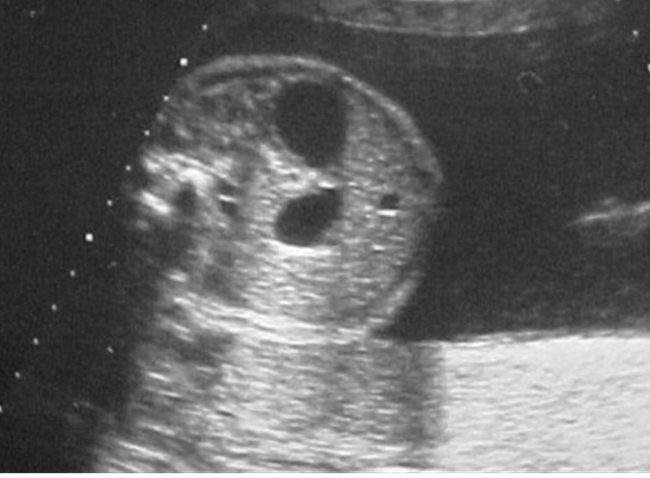

hydronephrosis